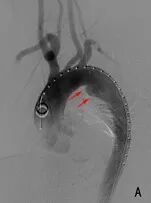

在数字减影血管造影机的精确引导下,周医生通过患者大腿根部的微小穿刺点,将覆膜支架系统沿血管轻柔而准确地输送至病变的胸主动脉。

支架在预定位置展开,既完美覆盖了血管内膜的破口,将肆虐的血流重新导入真腔,又巧妙地为通向大脑和上肢的重要分支血管留出了通道。

数小时后,当造影显示支架位置完美,主动脉血流恢复通畅,所有人都松了一口气——这颗“不定时炸弹”终于被成功拆除。

主动脉支架植入后,破口消失,主要血管分支通畅